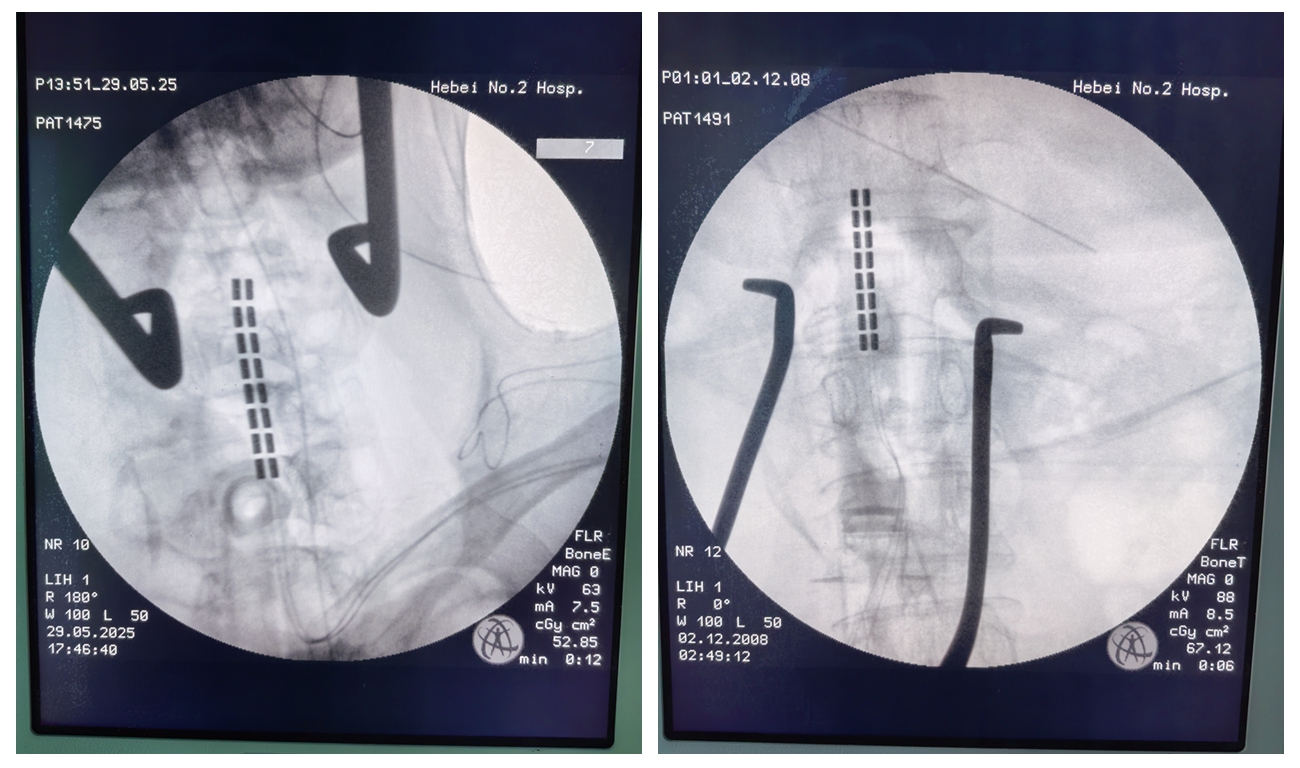

治疗新选择 | 河北医大二院神经外科运用脊髓电刺激术成功治疗脑出血后严重痉挛患者

近日,我院神经外科五病区为一例脑出血术后遗留严重痉挛性瘫痪的患者,成功实施脊髓电刺激术,帮助患者打破康复僵局,重获部分运动功能。 患者为51岁男性,脑出血术后半年仍处于朦胧状态,四肢严重痉挛,肌张力显著...